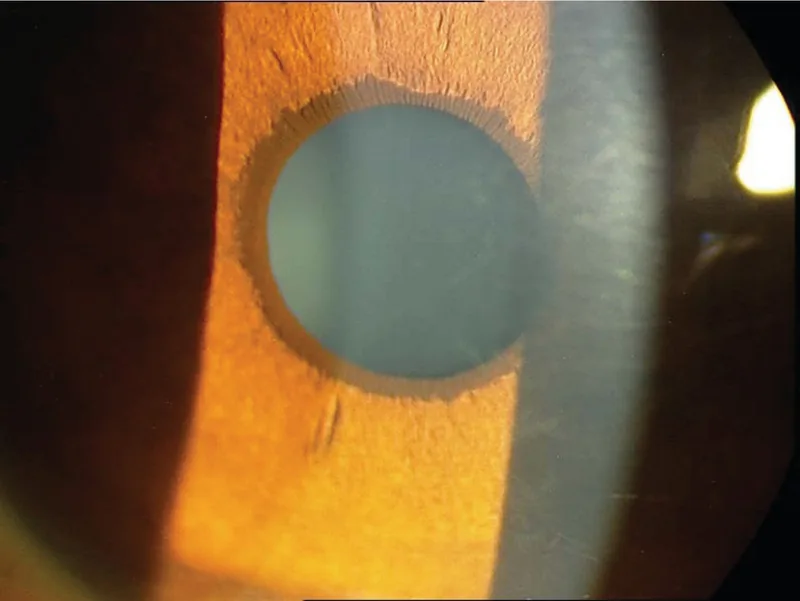

先天性ぶどう膜外反(Congenital Ectropion Uveae: CEU)は、出生時から存在するぶどう膜外反と、線維柱帯およびシュレム管の発育不全に起因する続発性緑内障を特徴とする稀な疾患である。別名として先天性虹彩外反症候群、原発性虹彩色素上皮増殖症がある。

先天性は出生時から存在し、前房内の原始内皮の退縮不全が原因で非進行性です。後天性は増殖糖尿病網膜症や中心静脈閉塞症に伴う線維血管膜の牽引で起こり、基礎疾患が治療されない限り進行します。先天性は片側性で小児に見られ、後天性は成人に多いのが特徴です。

CEU は主に臨床診断であり、以下の3要素に基づく。

両者とも片側性で瞳孔異常を呈しますが、ICE 症候群は中年女性に多く発症し、シュワルベ線を超える高い周辺虹彩前癒着(PAS)を特徴とします。CEU は出生時から存在し、周辺虹彩前癒着 は認められません。また ICE は進行性ですが、CEU のぶどう膜外反自体は非進行性です。